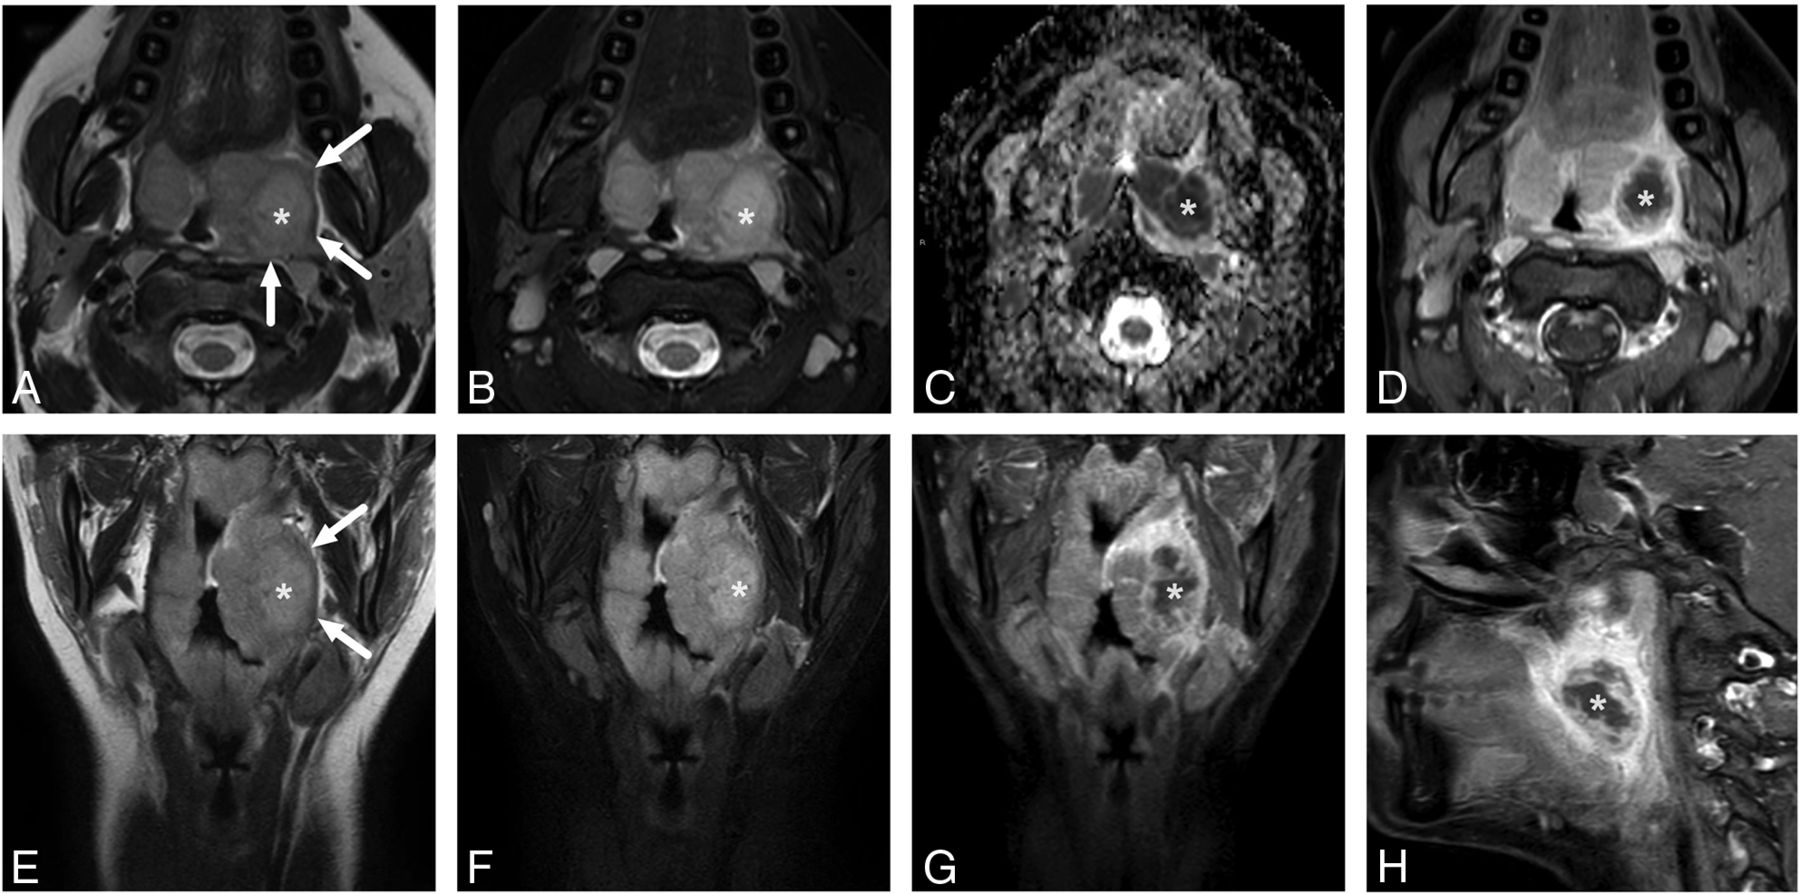

Uncomplicated PTA in an 18-year-old male patient with a sore throat. In-phase axial (A) and coronal (E) as well as fat-suppressed axial (B) and coronal (F) T2-weighted Dixon images reveal a slightly T2-hyperintense abscess (asterisk) lateral to the left palatine tonsil. The edematous pharyngeal constrictor muscle can be seen around the palatine tonsil (arrows in in-phase images A and E). The abscess shows restricted diffusion on the ADC map (C) and a nonenhancing core surrounded by an enhancing rim in axial (D), coronal (G), and sagittal (H) post-Gd fat-suppressed T1-weighted Dixon images.

Most abscesses have lower ADC values and higher T2SI than the tonsillar tissue itself. In some cases, abscess fluid can be so purulent that the T2SI is not very high (Fig 1). On the other hand, normal tonsillar tissue has a low ADC by virtue of high cellularity, so differentiating the abscess from the tonsil may be challenging. Although only 8% of the patients had higher ADCs and 11% of the patients had lower T2SI in the abscess than in the tonsil, in our experience, post-Gd T1-weighted images are required to delineate pharyngotonsillar abscesses accurately. Future studies should measure the diagnostic accuracy and interobserver agreement when using only DWI and T2-weighted imaging without a Gd-based contrast agent in cases of pharyngotonsillar abscesses.